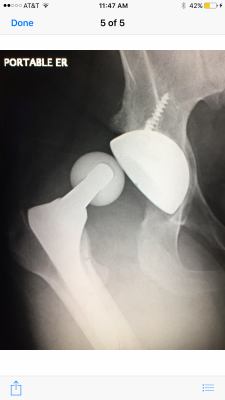

Last May my husband was putting on his shoes on the side of the bed when his hip replacement dislocated, and he fell to the floor in agony. Of course, he was alone in the house, and his cell was on the bureau on the other side of the room. Lucky for him, the house phone was on his nightstand, and he was able to call 911.